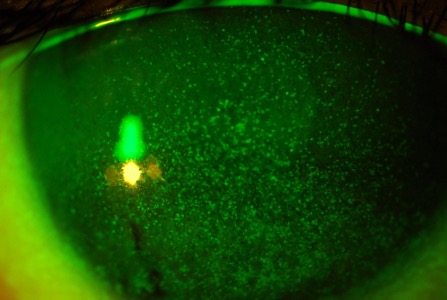

乾眼

市民選購隱形眼鏡時,可能經常聽到含水量這個名詞,有部份人甚至誤信鏡片含水量越高就越舒服這個說法,實情卻是鏡片含水量越高,配戴者越容易引發眼乾這個併發症。角膜比您的皮膚更需要水份滋潤,平時淚水會以一層薄膜覆蓋眼球表面,淚水不足,眼睛自然感到乾澀、痕癢。隱形眼鏡屬於外來物,少不免會影響淚膜的穩定性,加速其自身的揮發速度,所以很多隱形眼鏡配戴者都會受到乾眼症的困擾。乾眼症患者大多會選用人工淚液去緩解症狀,但這只能治標,要避免問題惡化,就先要找出問題根源,再對症下藥,例如更換更保濕的隱形眼鏡、縮短配戴時間、又或停用隱形眼鏡等等,方法各有不同。

乾眼

照片由香港理工大學眼科視光學院提供